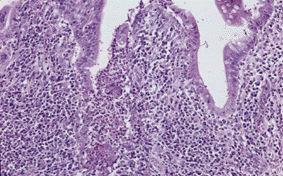

Caso de resección de patología gástrica de tipo inflamatoria que se presentó con hallazgos similares al cáncer avanzado

Enfermedad Inflamatoria - Ulcerativa/otros

estómago(región)/mas de dos

Micro